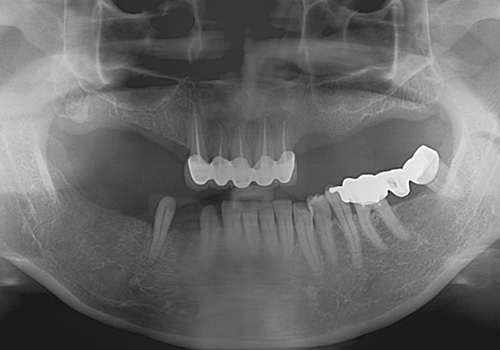

김○두님 임플란트 식립 전

2017년 7월

김○두님 임플란트 식립 후

2020년 6월 -